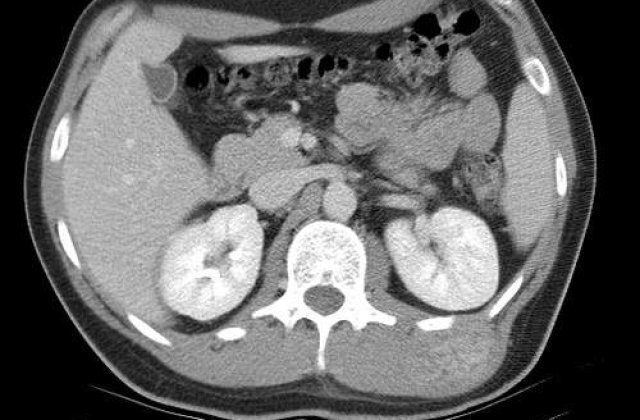

Tumora lui Nguyen Duy Hai, in varsta de 31 de ani, originar din provincia Lam Dong din centul tarii, s-a dezvoltat de cand acesta avea patru ani, la piciorul drept.

In pofida unei prime operatii pe care a suferit-o in urma cu 14 ani, tumora, desi benigna, nu a incetat sa creasca, ajungand la diametrul de un metru si cantarind 90 de kilograme.